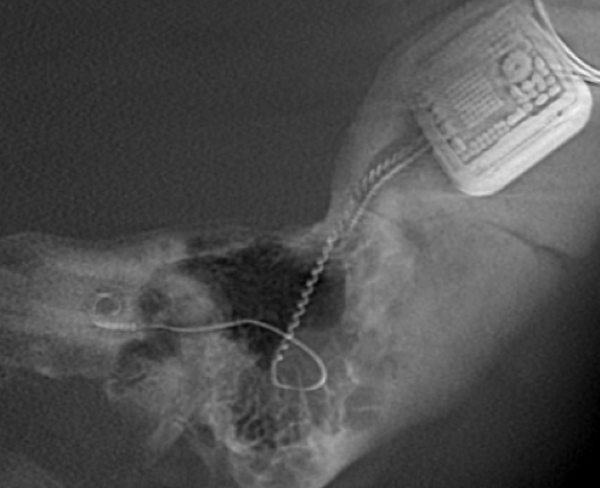

Both patients were imaged immediately with CBCT using SCANORA® 3Dx (Soredex, Tuusula, Finland). The field of view (FOV) was 140 x 165 mm and voxel size 0.2 mm. Imaging parameters were 90 kV, 8 mA, 4.00s. Standard 1 mm axial, coronal and sagittal reformations were made, as well as MIP and 3D reconstructions using OnDemand3D™ software (Cybermed, Seoul, South Korea).

CBCT proved to be optimal for imaging of these implants because of the superior bony delineation and nearly artefact free images. All four parts, i.e. the receiver stimulation part, extracochlear electrode implanted on the surface of the temporal bone, the extracochlear electrode plate and the intracochlear electrode array could be well imaged with CBCT.

On CBCT all four of the important parts of the implant were very well seen both on the axial slices and three dimensional surface reconstruction images. The implant is placed on magnetic plates, and the extracochlear part was seen in an abnormal separated position. The intracochlear electrode array showed no signs of separation in either of the cases. The intracochlear electrodes were well seen in both of the cases.

The optimal images of these two patients are shown in the radiographic illustrations in Figures 1-7.

Figure 4: 3D MIP image of patient 2.